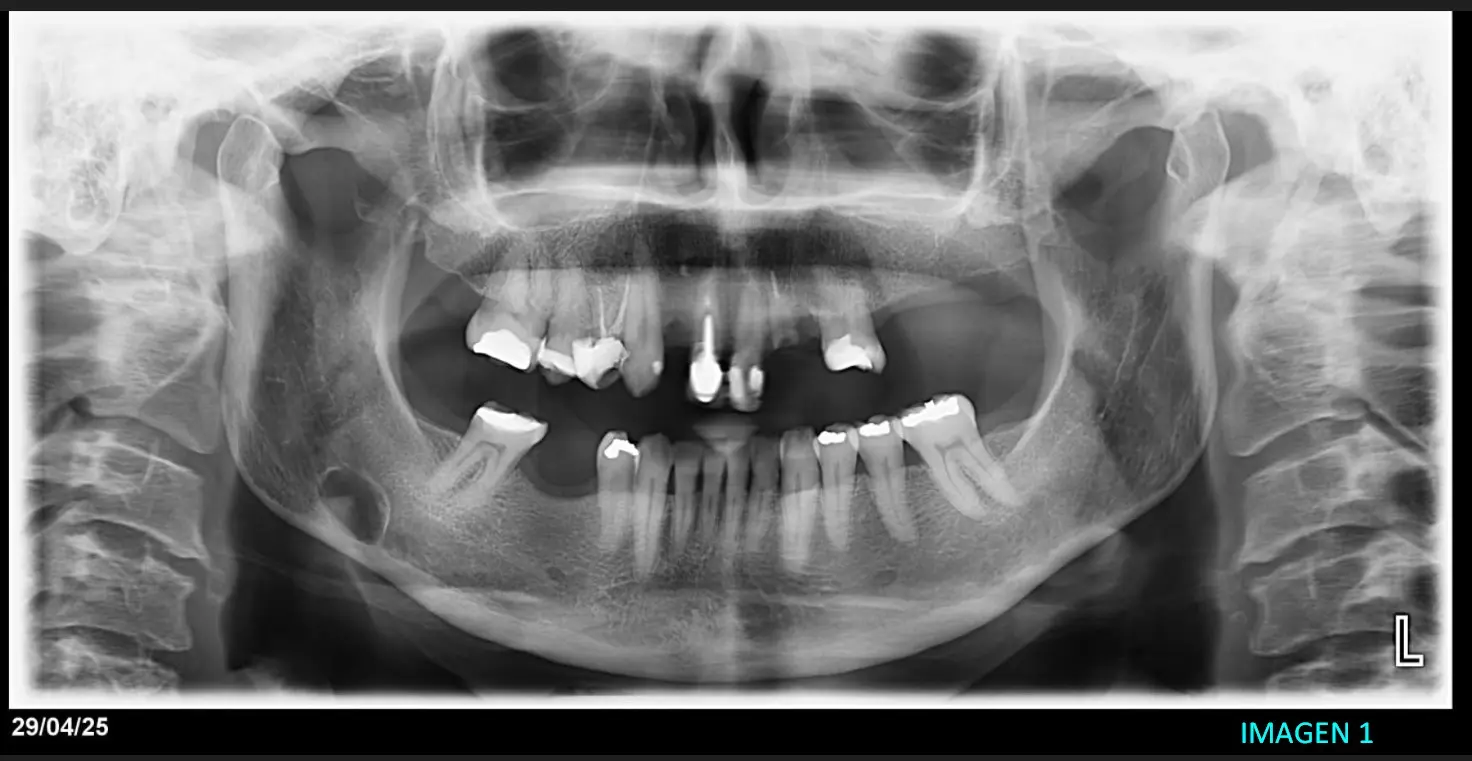

Se procede a realizar a paciente femenino de 54 años de una tomografía Cone Beam de maxilar inferior para control general. Luego de la realización de dicha tomografía y presentar el resultado nos consultan sobre una posible lesión que presenta la paciente y no se logra ver en la tomografía realizada. Procedimos a investigar el caso y comunicarnos con la paciente la cual nos muestra una Rx panorámica que se había realizado meses en otro centro de imágenes, en donde se observa imagen radiolúcida con forma redondeada ubicada específicamente en lado derecho cerca del ángulo de la mandíbula. Imagen 1

Presentamos cortes transaxiales y axiales donde logramos ver imagen de forma redondeada con bordes delimitante y con densidad hipodenso la cual se encuentra en región molar cerca de ángulo de la mandíbula por debajo del conducto dentario inferior derecho y hacia cara lingual. Presenta ausencia de cara ósea lingual Imagen 2, imagen 3 e imagen 4.